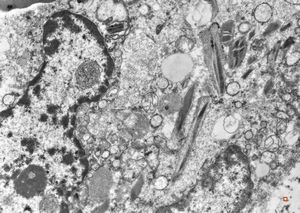

bone marrow - crystalloid inclusions Charcot-Leyden crystals formation

bone marrow - crystalloid inclusions Charcot-Leyden crystals formation v.s.